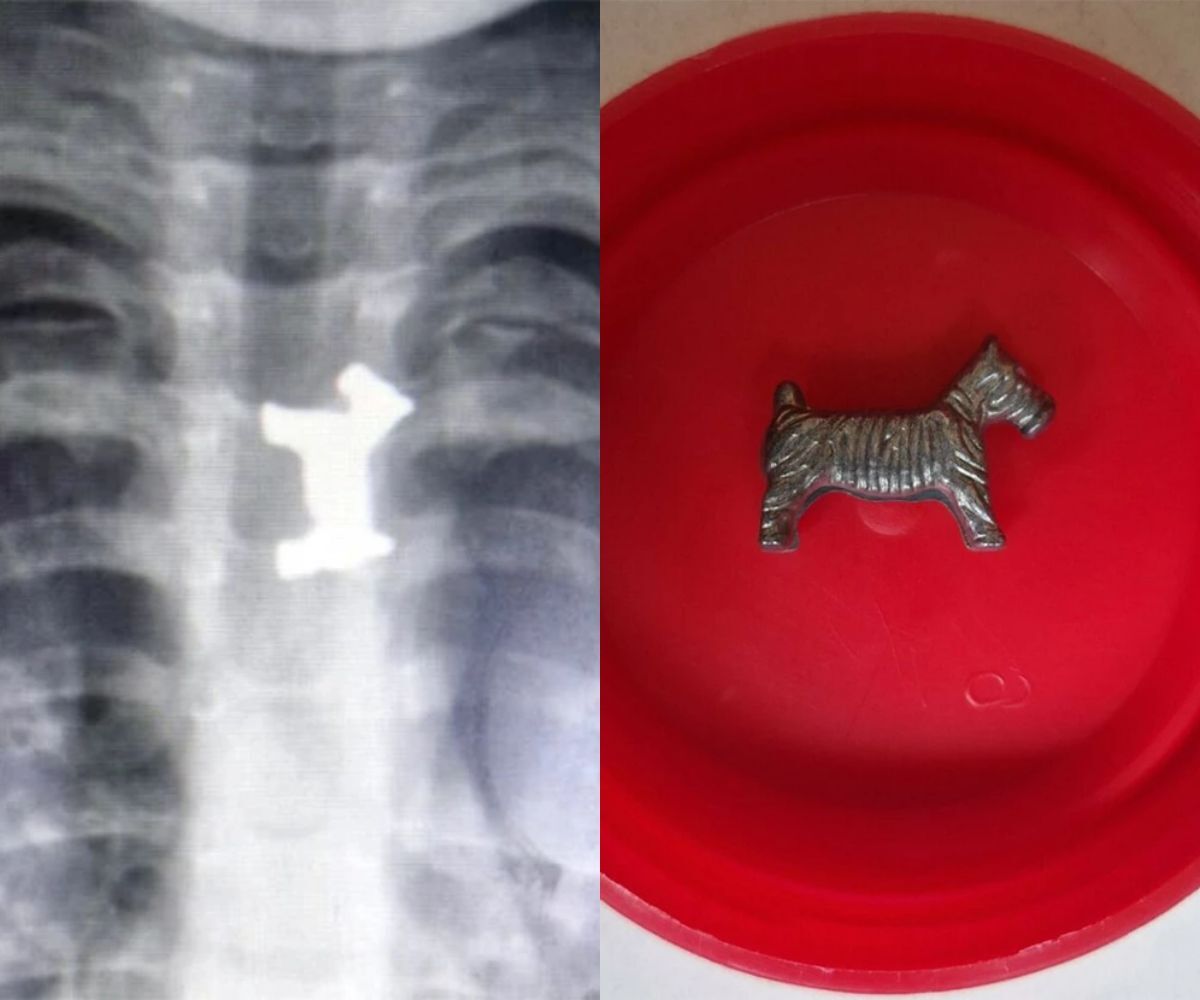

Όπως μεταδίδει η ΕΡΤ, το αγοράκι εμφάνισε σιελόρροια και οι έντρομοι γονείς του το πήγαν στο Γενικό Νοσοκομείο Σερρών όπου εξετάστηκε από τους γιατρούς. Η ακτινογραφία του 4χρονου παιδιού έδειξε ότι είχε καταπιεί και είχε σφηνώσει στον οισοφάγο του ένα μεταλλικό παιχνίδι. Κατά συνέπεια, λόγω της σοβαρότητας της κατάστασής του αποφασίστηκε η διακομιδή του στο Ιπποκράτειο Νοσοκομείο Θεσσαλονίκης.

Ο μικρός νοσηλεύεται προληπτικά και είναι καλά στην υγεία του.